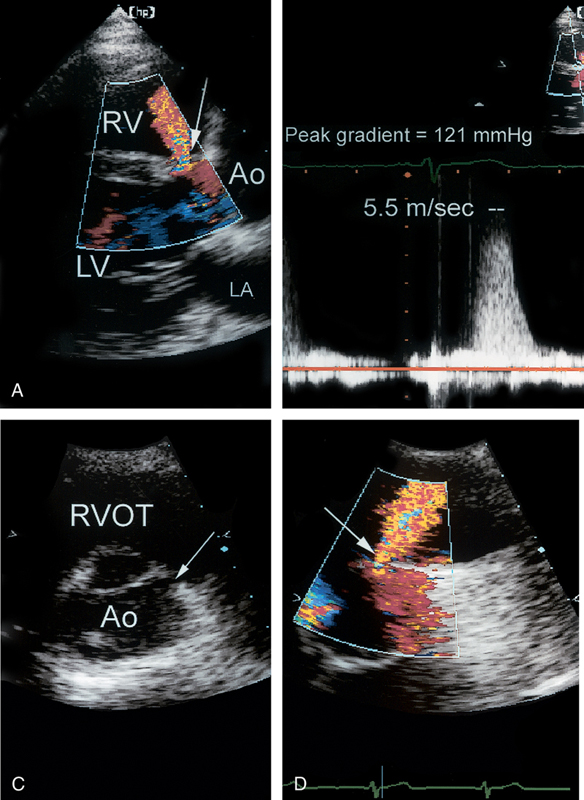

فحوصات تشخيصية لبعض امراض القلب والشرايين التاجية